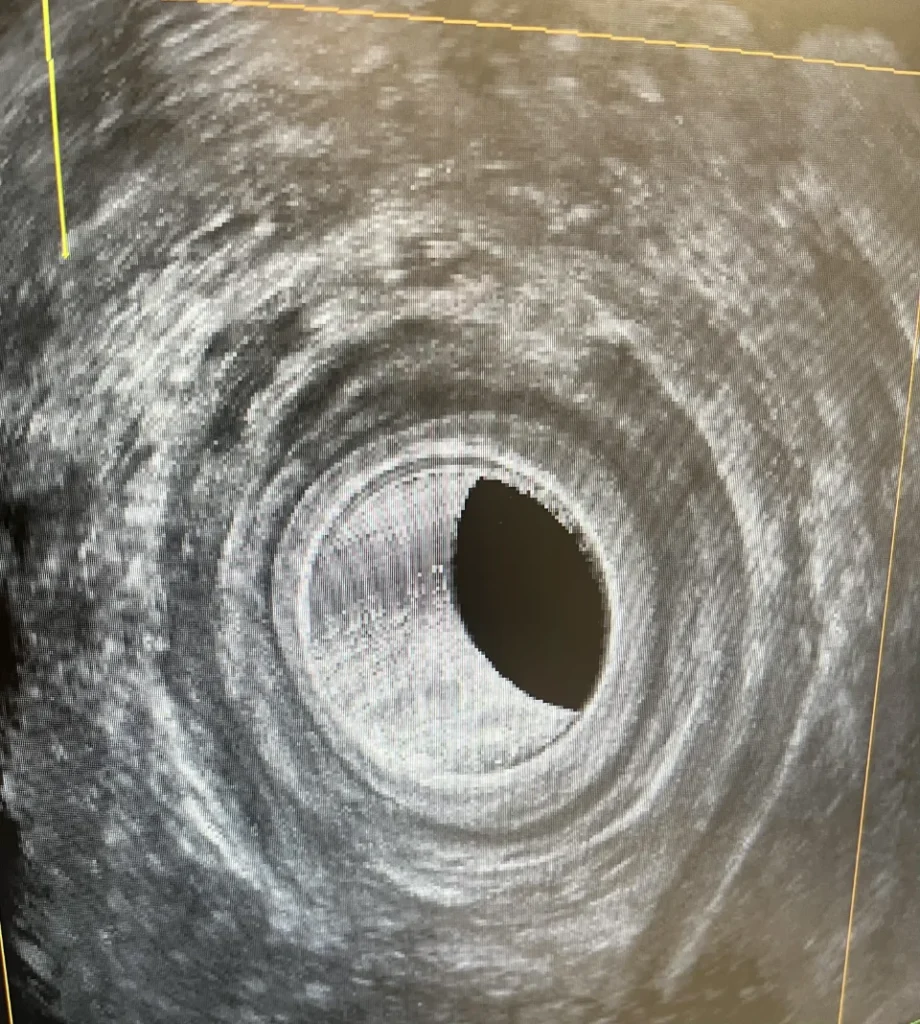

While there are other methods to treat an anal fistula that don’t involve cutting any sphincter muscle, but these have much lower success rates. An anal ultrasound, especially one with a 3D reconstruction, gives the surgeon a 3 dimensional roadmap to help plan surgery. It helps identify the internal opening and if secondary tracts have arisen.

The ultrasound shows the surgeon the anatomy of where the tracts are and how much sphincter muscle is involved. Importantly, it also shows how much muscle will be left if the tract is suitable to be layed open.

An 3D ultrasound image demonstrating a right sided fistula arising from the midline of the posterior canal.